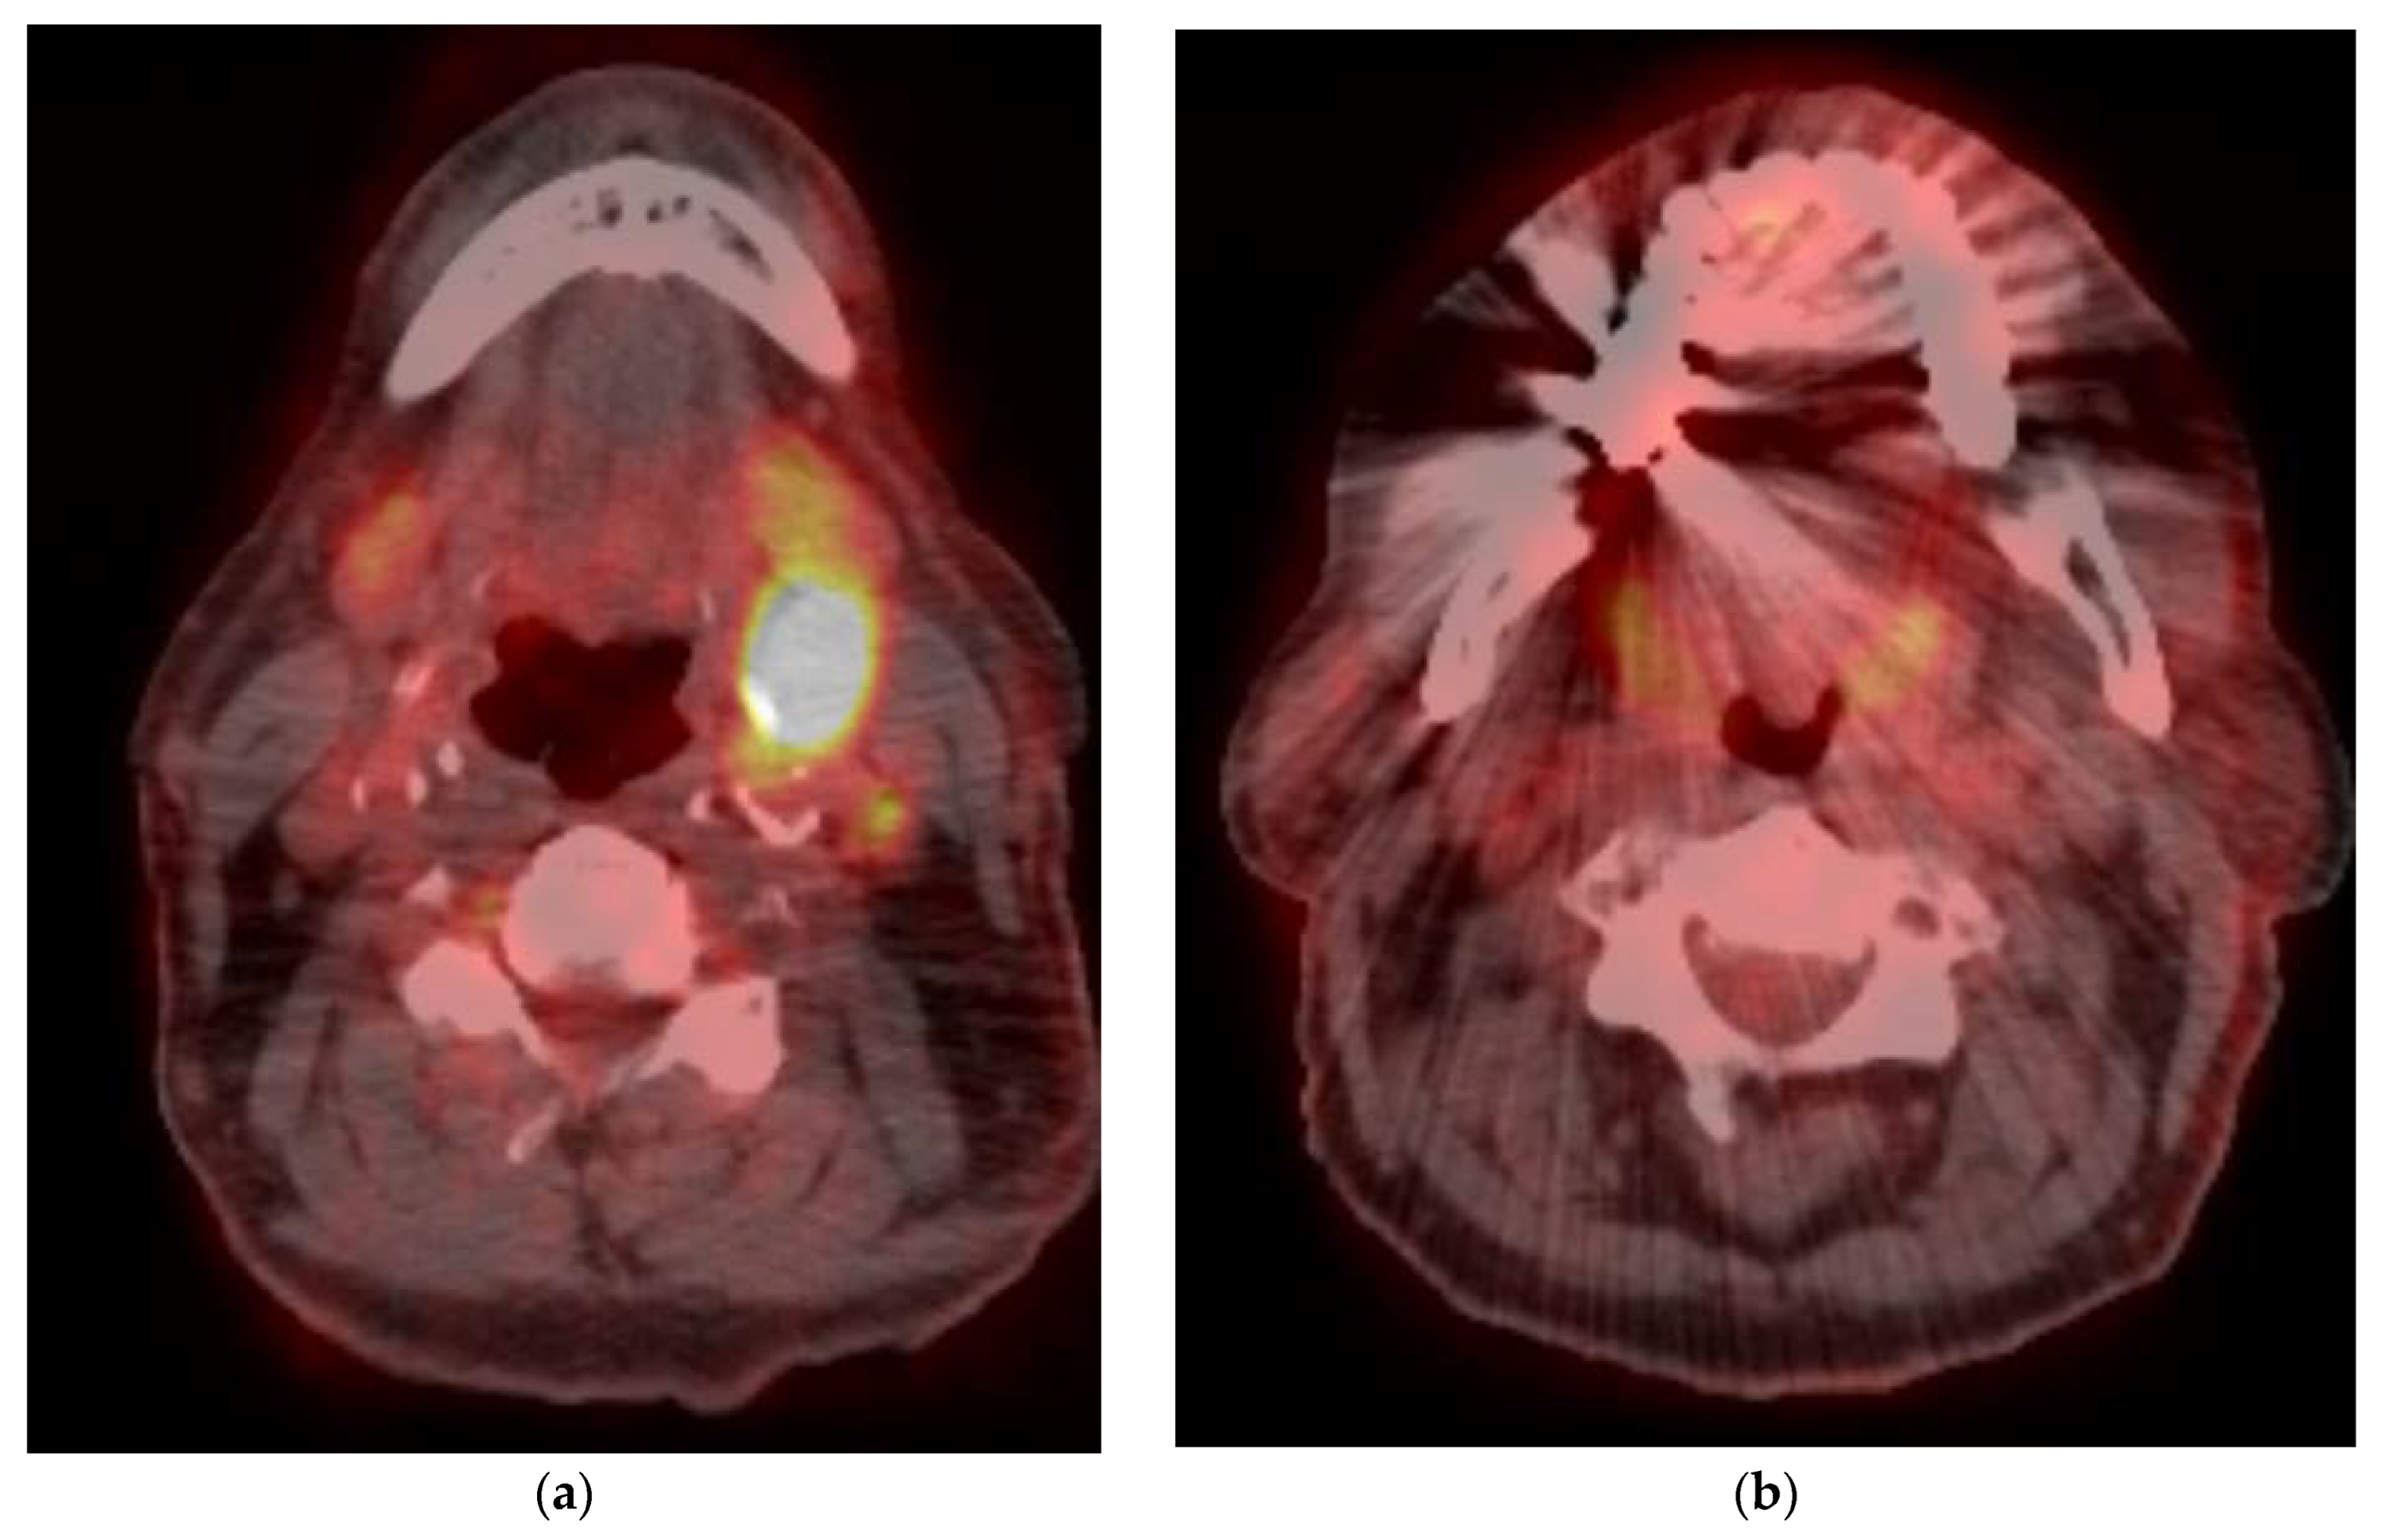

5. Imaging of Oropharyngeal Cancers

8.2. Response Assessment